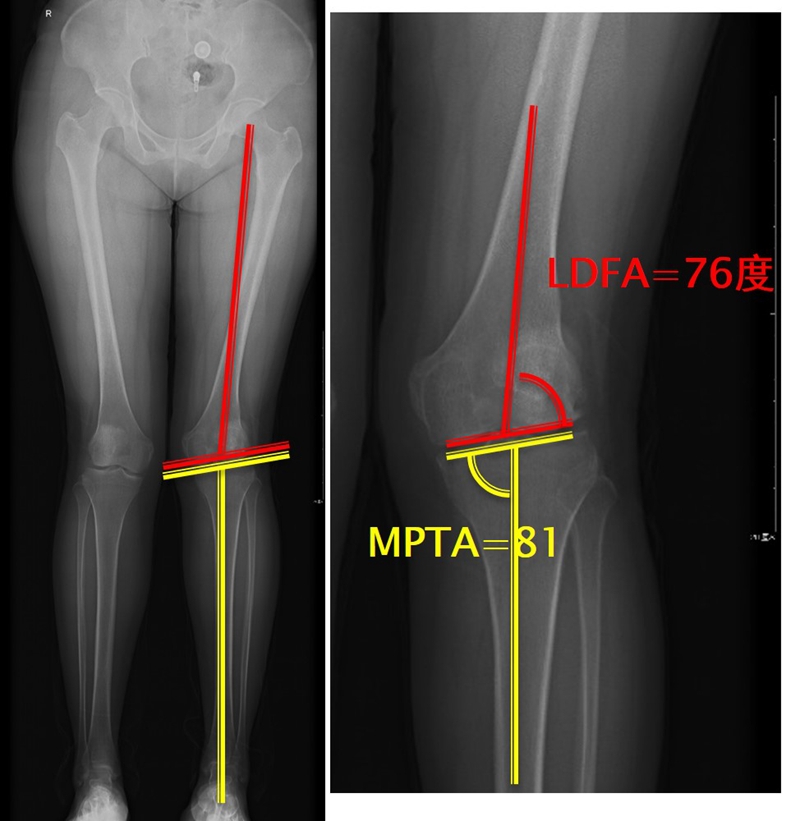

步骤二:判断畸形部位

量股骨远端外侧角和胫骨近端内侧角,判断畸形在股骨、胫骨还是关节内。此患者股骨侧有畸形,LDFA=76°,MPTA=81°,无关节内畸形。

此患者计划股骨内侧闭合楔,胫骨内侧开放楔。

以股骨侧合页为旋转中心,以股骨头中心到合页的距离为半径,进行旋转,直到该线段与目标力线相重合,此时重合角度即为股骨需要闭合的角度,同时胫骨侧也能计算出开放的角度。此患者需要股骨闭合14°,胫骨开放8°。